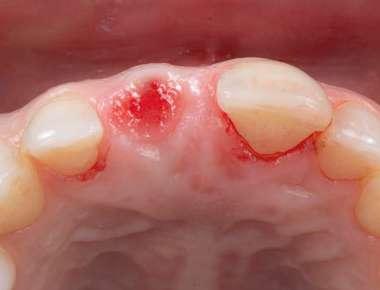

na paciente de 35 años (Figura 1) fue remitida a la Clínica de Odontología Reconstructiva de la Universidad de Zúrich debido a una infección crónica en el diente 11 y con expectativas estéticas muy altas. El diente 11 había sufrido un trauma hace 10 años y había sido tratado con multiple endodoncias sin éxito. El diente presentaba un absceso bucal (Figura 2), una bolsa periodontal aislado de 9 mm, y una ausencia de la tabla vestibular ósea (Figura 3). El diagnóstico se estableció como una fractura radicular vertical, lo que resultó en un pronóstico pobre. El plan de tratamiento consistió en una extracción combinada con preservación alveolar, colocación de implante diferido con injerto de tejido conectivo, una corona cerámica implantosoportada en 11 y una nueva carilla de cerámica para el diente 21.

El diente 11 fue extraído (Figura 4), seguido por la preservación alveolar. Se realizó un injerto pediculado de espesor parcial rotado del paladar (Figura 5), junto con una membrana de colágeno reabsorbible, un xeno-injerto bovino y cianoacrilato sellando al alveolo (Figura 6). La provisionalización consistió en un puente adhesivo de resina con dos alas de metal. El alveolo se dejó cicatrizar durante 6 meses, después de los cuales se tomó una impresión digital así como un escáner CBCT (Figura 7). Se llevó

a cabo una planificación digital para una cirugía guiada de implante en una posición protéticamente ideal (Figura 8). El implante 11 se colocó completamente guiado a través de una férula (Figura 9). Las dimensiones del reborde alveolar eran ideales para la colocación del implante en una posición atornillada (Figura 10), al igual que la calidad del hueso cicatrizado. Un injerto de tejido conectivo subepitelial fue estabilizado ocluso-bucalmente al implante (Figura 11) y el puente adhesivo fue recementado (Figura 12). Después de 3 meses de cicatrización, se realizó una restauración provisional y se acondicionó adecuadamente para dar forma al perfil de emergencia, imitando el del diente adyacente (Figura 13). Después de una fase provisional, se tomó una impresión analógica individualizada para el implante 11 y el diente 21 (Figura 14). El laboratorio fabricó una corona implantosoportada de zirconio con cerámica estratificada para el 11 y una carilla laminada feldespática para el diente 21 (Figura 15). Ambas restauraciones fueron colocadas en la paciente y mantenidas. La paciente quedó muy satisfecha con el resultado estético de las restauraciones (Figuras 16, 17). Después de 2 años, el implante permanece saludable con el hueso marginal estable (Figura 18) y una buena calidad y cantidad de tejido blando.